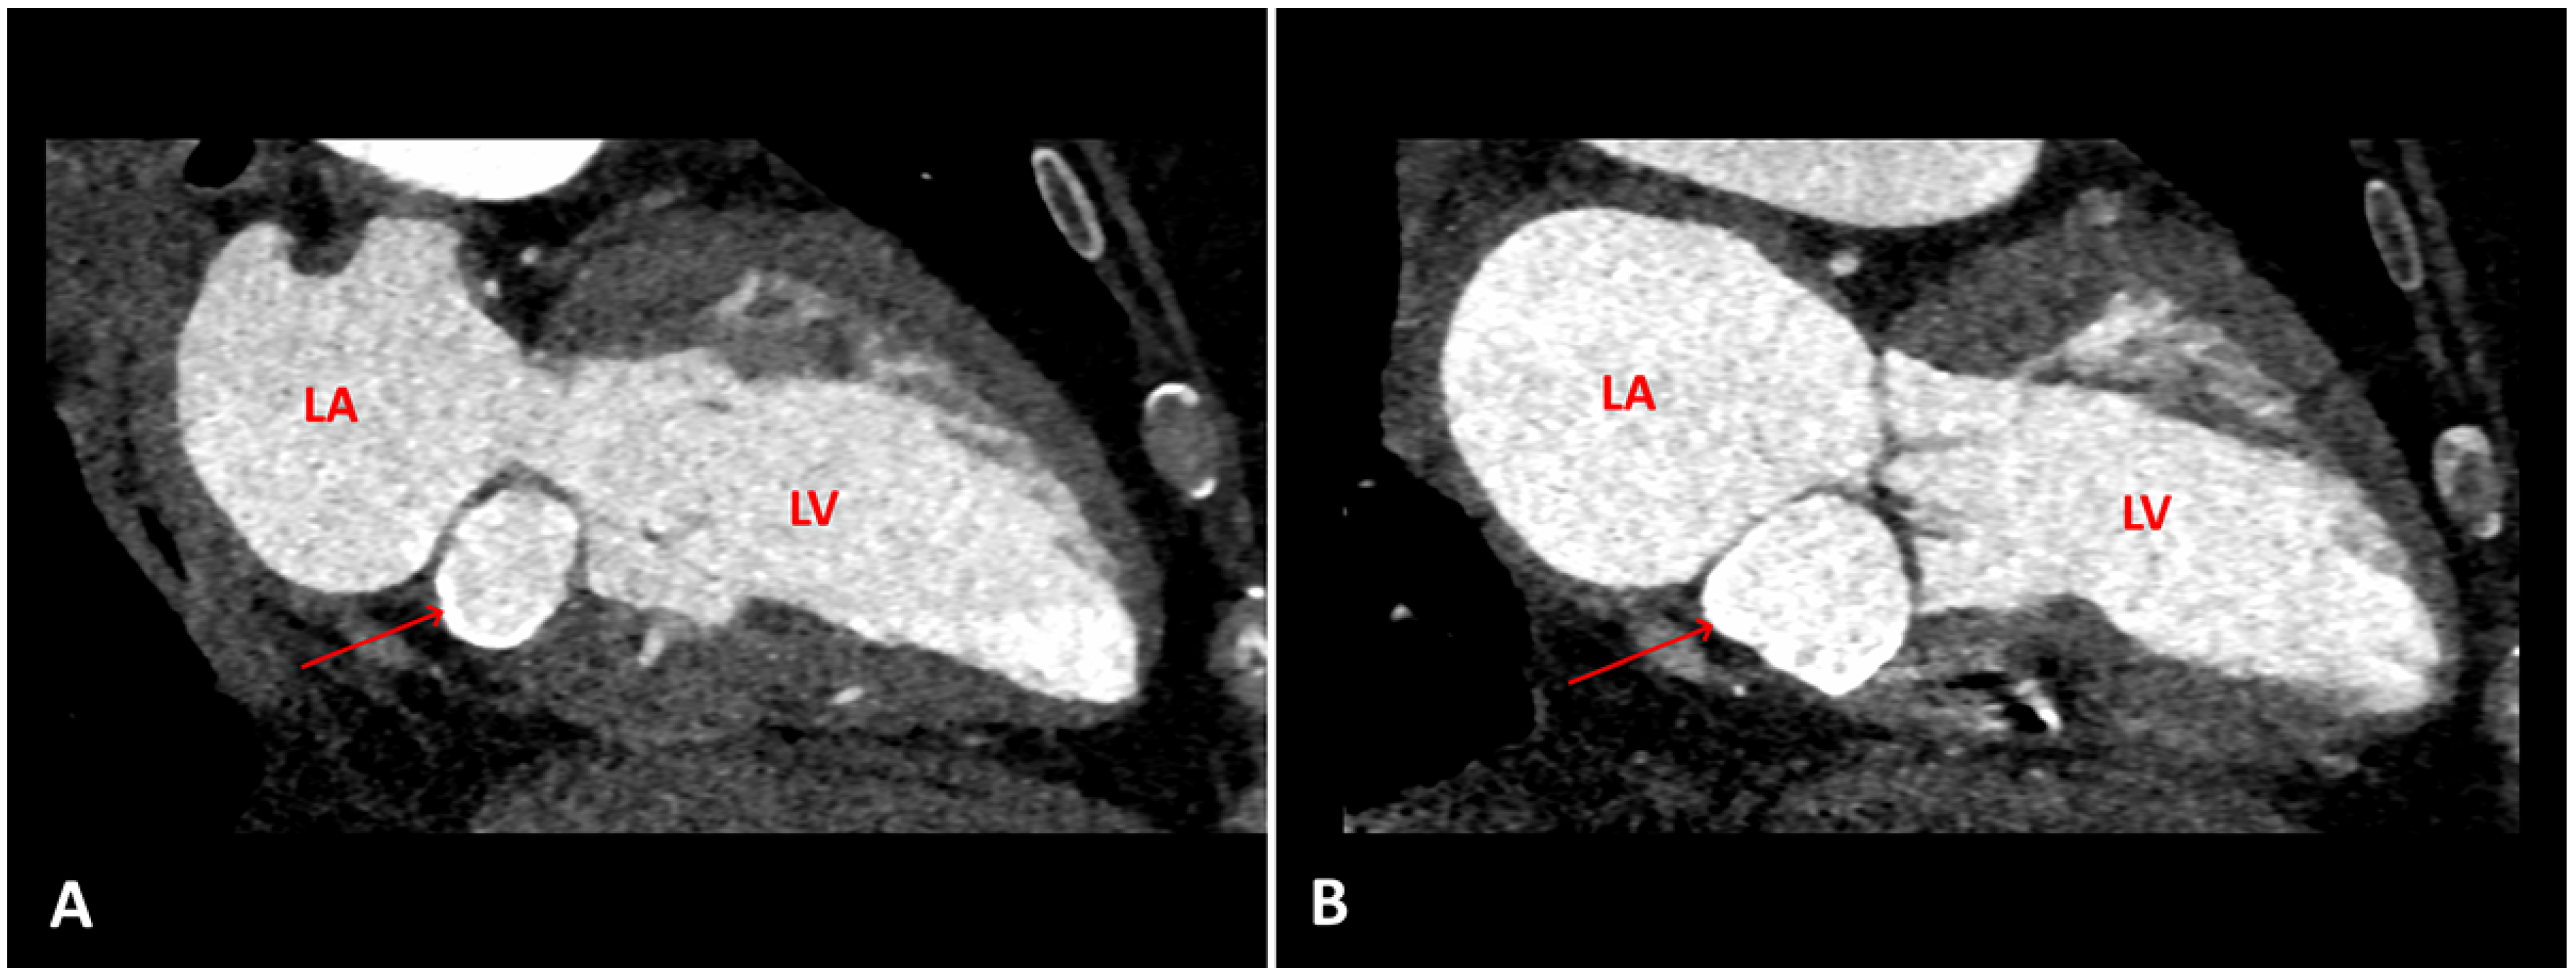

A routine transthoracic echocardiogram (TTE) performed 4 years previously, with a view to orthopaedic surgery, had revealed a cardiac mass attached to the posterior mitral annulus with a mitral mean gradient of 6 mm Hg (at a heart rate of 80 beats per minute). At that time cardiac magnetic resonance imaging (cMRI) and computed tomography (CT) were performed and the diagnosis of caseous calcification of the mitral annulus was established (Figure 1). Two years after the initial diagnosis, the patient developed third degree atrioventricular block for which a dual-chamber pacemaker was implanted. The patient was asymptomatic for a further 2 years until she developed an episode of acute severe dyspnoea.

In the emergency department the patient’s vital signs (oxygen saturation 88%), clinical examination (tachypnoea, orthopnoea, bilateral lung crackles), laboratory tests (elevated N-terminal pro-B-type natriuretic peptide [NT-proBNP]) and chest X-ray (lung congestion) confirmed the diagnosis of acute heart failure, albeit of unclear aetiology: her blood pressure was only mildly increased, mild troponin elevation argued against an acute coronary syndrome, haemoglobin levels and heart rate were stable (Table 1). The patient was admitted for oxygen supplementation and intravenous diuretics with rapid recovery ensuing in a few days. A TTE documented normal heart function but an increase in the size of the cardiac mass ( 46 mm × 31 mm compared with 36 mm × 27 mm 4 years before), the mean gradient across the mitral valve was unchanged at 6–7 mm Hg at a heart rate of 65 bpm (Figure 2) The mitral valve area obtained by two-dimensional planimetry from the parasternal short axis view was 1.2 cm2 (Figure 3B). No other significant valve disease was found. Transoesophageal echocardiography (TOE) showed moderate mitral stenosis. The mitral valve orifice measured by three-dimensional planimetry was 1.4 cm2 (Figure 3A). Remarkably, there was an increase in the mean diastolic mitral gradient from 6 mm Hg at the time of the TTE to 13 mm Hg on TOE, probably due to a higher heart rate of 85 bpm (Figure 5). A CT scan showed an increased size of the mass (Figure 4). Due to the frailty of the patient and in accordance with her wish not to undergo any invasive treatment, surgery was not proposed. The patient was discharged before being admitted 2 months later for another episode of acute heart failure treated with intravenous diuretics. The therapeutic attitude was altered and at this time the patient was again discharged for ambulatory follow up for treatment adjustment and only symptomatic management if acute heart failure happens again.

Figure 4. A. Computed tomography (CT) scan, two chambers, at the time of diagnosis. B. CT scan, same view, 4 years later, showing the increasing size of the (arrows). LV = left ventricle, LA = left atrium